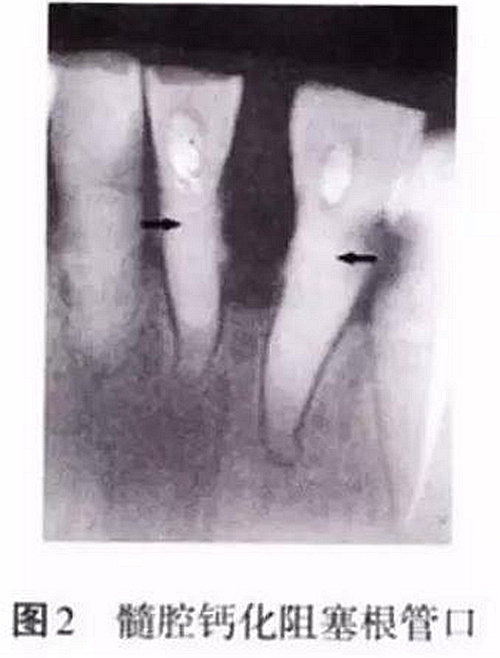

髓腔的形態(tài)非一成不變,年齡的增長(zhǎng)、外界物理和化學(xué)刺激、齲損等都會(huì)引起髓腔形態(tài)的改變,如髓腔體積變小、髓室頂和底的距離減小、髓腔鈣化阻塞根管口等,都會(huì)增加開(kāi)髓難度(圖2)。術(shù)前如檢查不充分,未考慮髓腔的生理病理變化,并采取相應(yīng)的治療措施,常會(huì)導(dǎo)致在尋找根管口的過(guò)程中破壞髓室底,甚至出現(xiàn)穿孔。